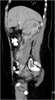

Extension of retroperitoneal mass

Posterior mediastinal lesion

May Cause